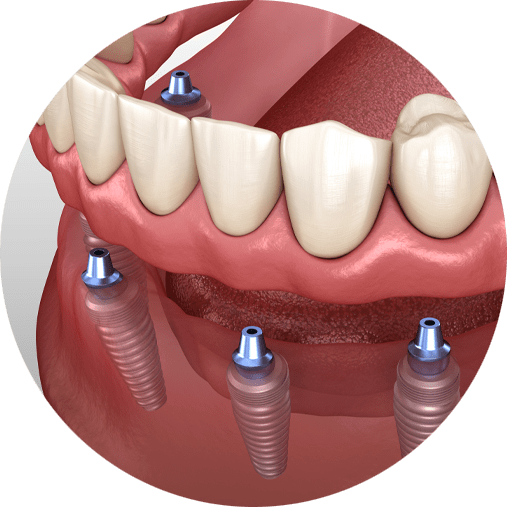

Dental Implants are an excellent investment in an individual’s medical and psychological well-being. Advanced Dental Care believes finances must not be an obstacle to obtaining this important health service from our team. Therefore, at our multiple locations in New York, we offer $500 toward your full mouth dental implant cost in addition to your free consultation. Our centers provide a variety of payment and financing options to ensure the affordability of our treatments, including our new patient promotion of $179 comprehensive exam, x-rays and cleaning. We encourage you to contact our office today to learn about your affordable financing and warranties.